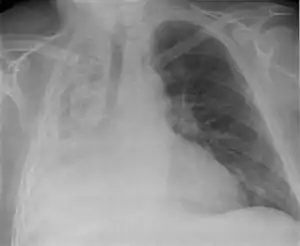

Atelectazie

Atelectazia, sau sindromul de condensare pulmonară retractilă, este o maladie, caracterizată de lipsa gazului din alveole, datorită colapsului alveolar sau a consolidării lichidului.[2] Condensarea pulmonară retractilă reprezintă o modificare survenită la nivelul parenchimului pulmonar, în care se asociază două elemente:

- colaps al alveolelor pulmonare, ce devin aplatizate ca urmare a unui defect de ventilație în teritoriul respectiv (dar cu păstrarea perfuziei), prin obstrucția bronhiei corespunzătoare;

- existența unui fenomen de retracție: teritoriul pulmonar respectiv este diminuat ca volum și antrenează, într-un proces de retracție, și zonele vecine.

Atelectazia este adesea martorul unei leziuni bronșice obstructive și presupune control bronhoscopic. O atelectazie instalată rapid poate fi secundară unui corp străin intrabronșic, iar o atelectazie instalată progresiv poate fi un semn de tumoră bronșică (neoplasm) sau mediastinală, ori de tuberculoză.

Poate afecta o parte sau întreg plamanul. Este o afecțiune în care alveolele sunt dezumflate, distinctă de consolidarea pulmonară.[2]